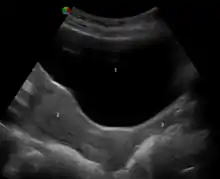

![]() Human vagina; normal canal (left) and canal during menopause (right) | |